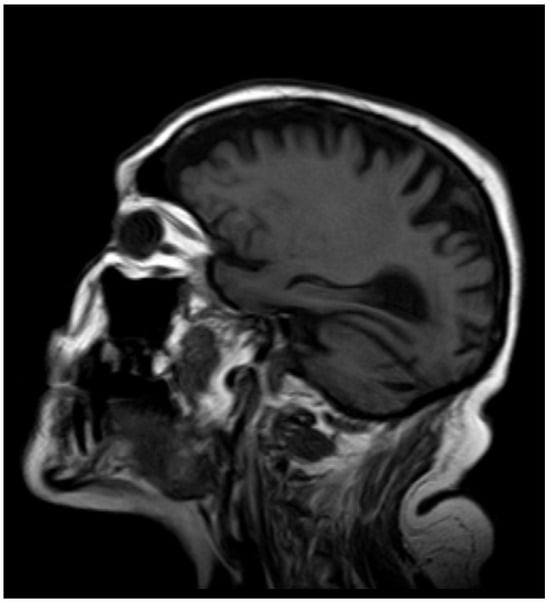

2. Case Report

2.2. Current Disease

2.3. Additional Tests